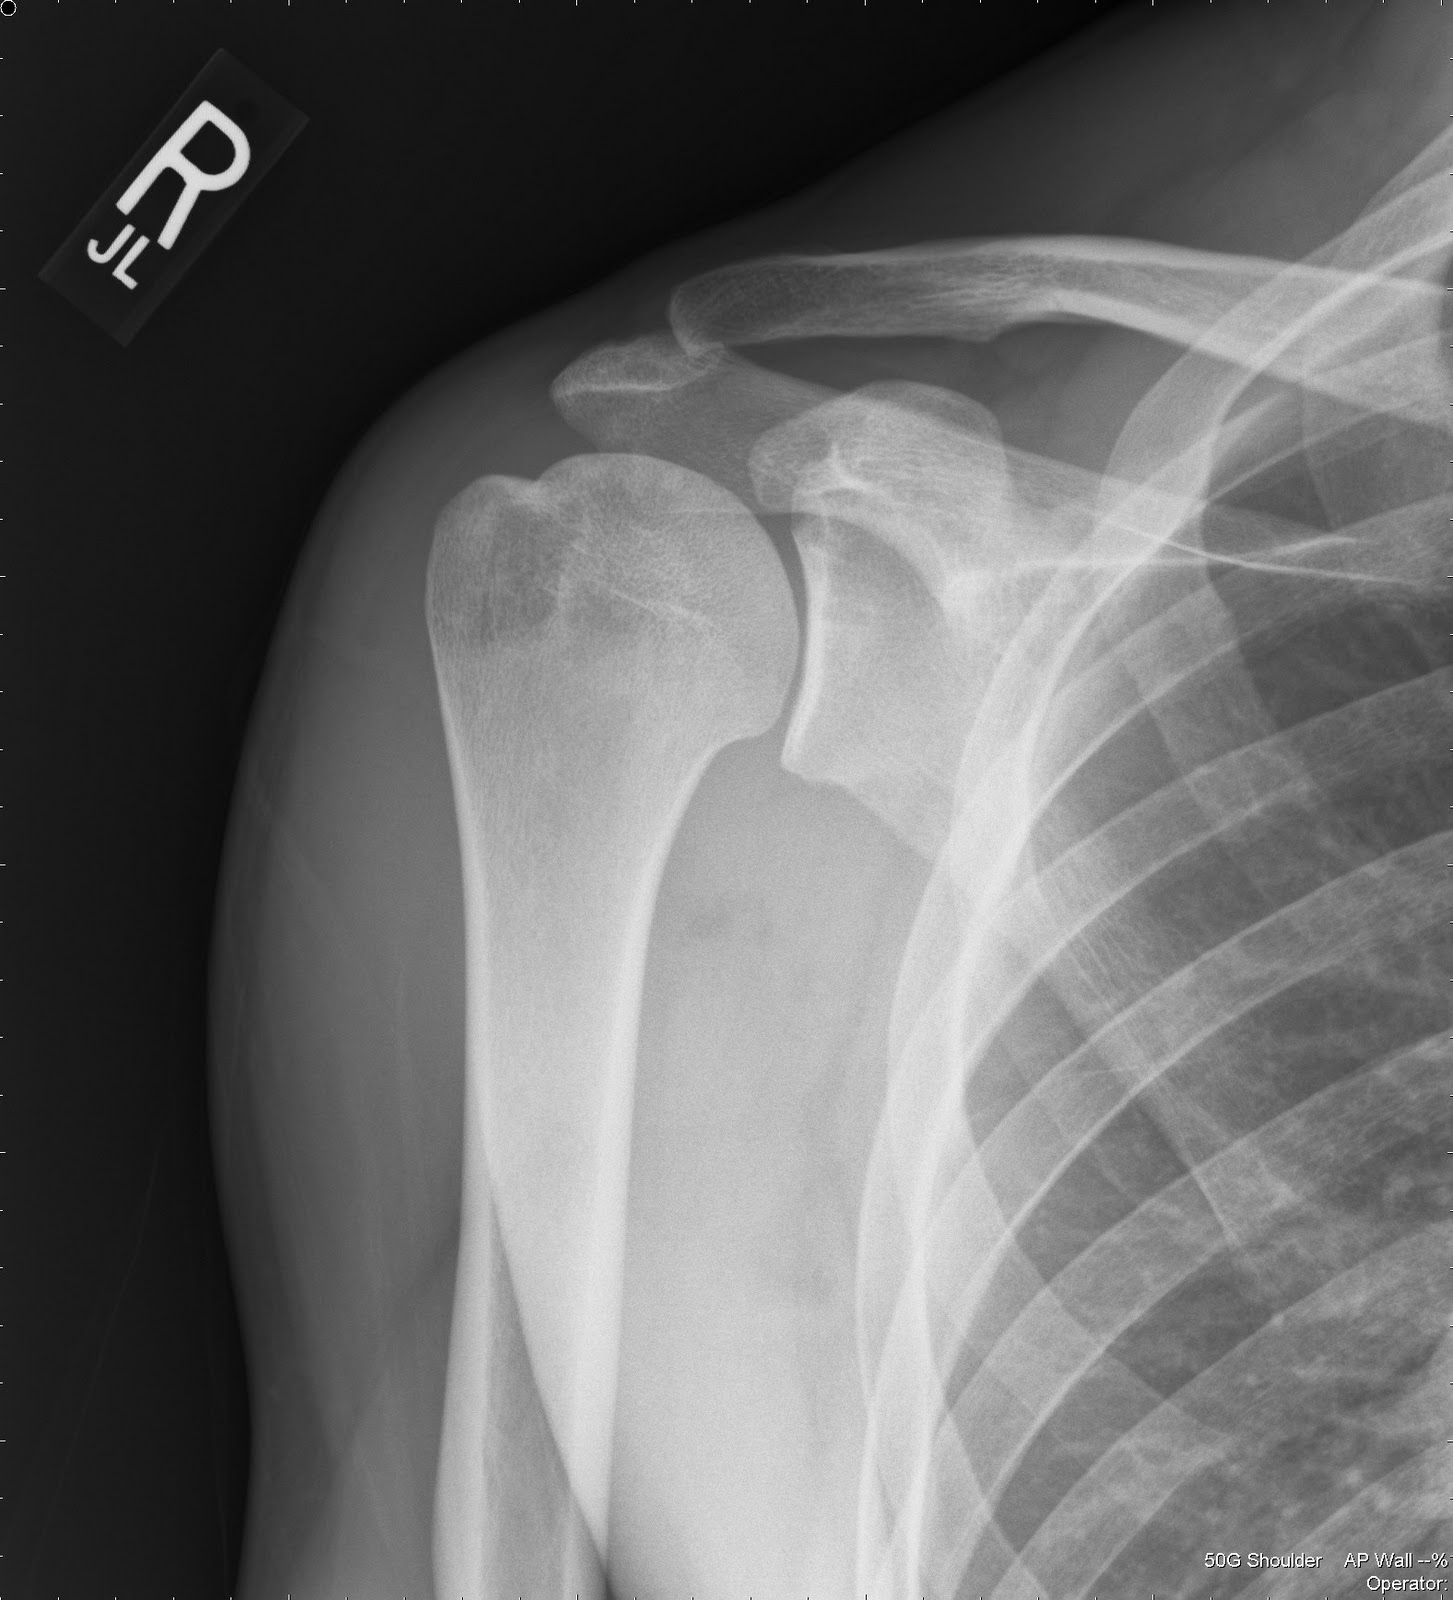

NORMAL SHOULDER 5

NORMAL SHOULDER 5 Shoulder X Ray Paediatric Assessing and diagnosing shoulder injuries in pediatric and adolescent patients. Diagnosis is confirmed with plain radiographs of the shoulder. The shoulder girdle is composed of three bones (the clavicle, scapula, and proximal humerus) and four articular surfaces. One is able to visualize 90% of posterolateral humeral head defects. Treatment is usually nonoperative in younger patients due to the remodeling potential. Shoulder X Ray Paediatric.

Normal Paediatric Shoulder 15 year old male wikiRadiography Shoulder X Ray Paediatric One is able to visualize 90% of posterolateral humeral head defects. The shoulder girdle is composed of three bones (the clavicle, scapula, and proximal humerus) and four articular surfaces. Diagnosis is confirmed with plain radiographs of the shoulder. Sports medicine at nationwide children’s hospital. Assessing and diagnosing shoulder injuries in pediatric and adolescent patients. Treatment is usually nonoperative in younger. Shoulder X Ray Paediatric.